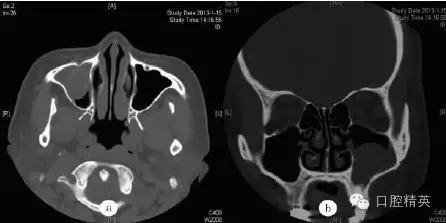

鼻竇CT檢查示:右側(cè)尖牙牙根處有一類(lèi)圓形軟組織密度影(圖a),病變向上進(jìn)入右側(cè)上頜竇,其內(nèi)見(jiàn)弧形線狀高密度影,鄰近牙槽骨壓迫性骨吸收(圖b)??紤]為根尖囊腫并發(fā)感染(右)。

圖a:術(shù)前水平位CT檢查顯示右側(cè)上頜竇黏膜囊腫,中央有類(lèi)圓形影;圖b:術(shù)前冠狀位CT檢查顯示右側(cè)上頜竇黏膜囊腫并根尖骨質(zhì)吸收,含類(lèi)圓形影;